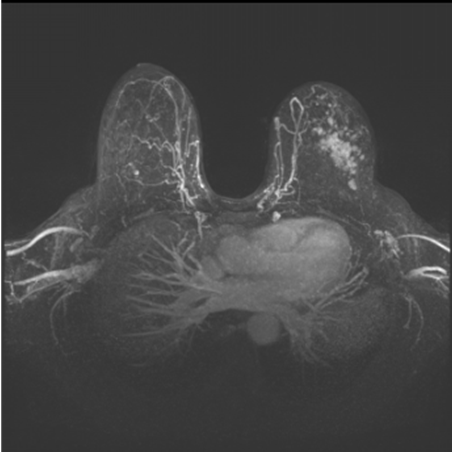

Магнитно-резонансная томография молочных желез

МРТ – метод диагностики, основанный на получении изображений внутренних органов с помощью радиоволн и сильного магнитного поля. Главное противопоказание к выполнению МРТ – наличие металлических конструкций в теле пациентки, в том числе кардиостимуляторов. МРТ – высокотехнологичный метод диагностики, широко применяемый за рубежом, но пока в России он редко используется для диагностики заболеваний молочных желез. Причинами являются высокая цена исследования, ограниченное число томографов в различных регионах страны и самое главное – недостаток профильных специалистов, которые правильно интерпретируют полученные МР-данные.

Показаниями для МРТ молочных желез являются высокая маммографическая плотность, наличие имплантов. Также это метод выбора у женщин с выявленной мутацией генов BRCA1 и BRCA2.

(Смотрите раздел «Факторы риска развития рака молочной железы»). В определенных случаях МРТ позволяет выявить раки, неопределяемые на МГ и УЗИ. Опытный врач-онколог или диагност знает, в каких случаях необходимо выполнение МРТ.

Рис.13 МР-томограмма рака молочной железы

Как проводится МРТ молочных желез?

Исследование проводится с контрастированием. Это значит, что вам в локтевую вену установят катетер и подключат к автоматизированному инжектору, через который в нужный момент введут контрастное вещество (в некоторых учреждениях введение контраста проводят вручную). У женщин репродуктивного возраста МРТ выполняется строго на 6–12 день менструального цикла. Это связано с тем, что во вторую фазу железистая ткань активно накапливает контрастное вещество, что может затруднять диагностику. После наступления менопаузы МРТ молочных желез можно проводить в любой день.

МРТ позволяет врачу-диагносту увидеть подмышечные, подключичные лимфатические узлы и даже парастернальные, которые невозможно определить при УЗИ и тем более при МГ.